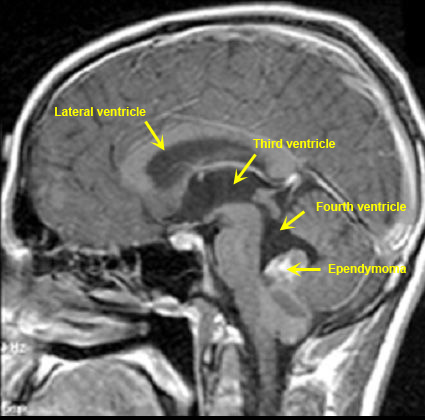

Obstructive Hydrocephalus / Ependymoma in fourth ventricle

Case 2:

Child with ependymoma arising within the fourth ventricle obstructing the outflow of CSF from the fourth ventricle resulting in obstructive hydrocephalus with enlargement of aqueduct, third ventricle and lateral ventricles.

Imaging findings:

Figure 2. Post-contrast sagittal T1 wtd. MRI